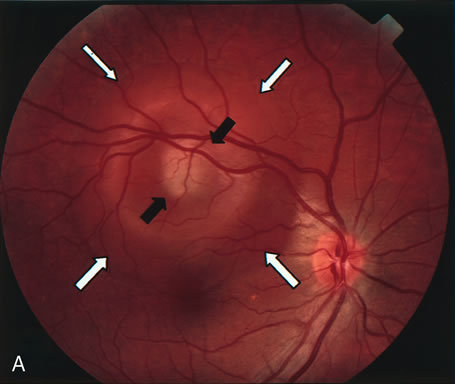

Gentamicin and tobramicin toxicity, which often result from inadvertent injection into the vitreous during cataract surgery, cause devastating retinal damage. In areas where high concentrations of gentamicin reach the retina there is obliteration of the retinal vasculature and ischemic necrosis of the retina (Fig. 43).269,270